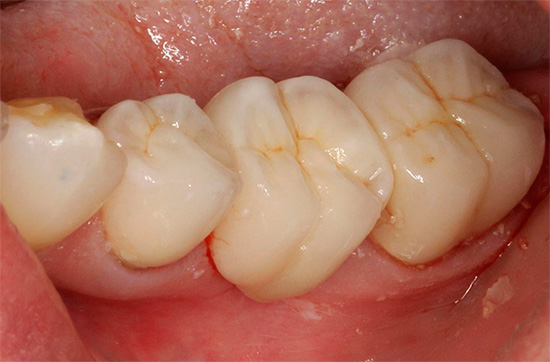

Nella foto - tipico carie delle fessure con manifestazioni esterne minime: